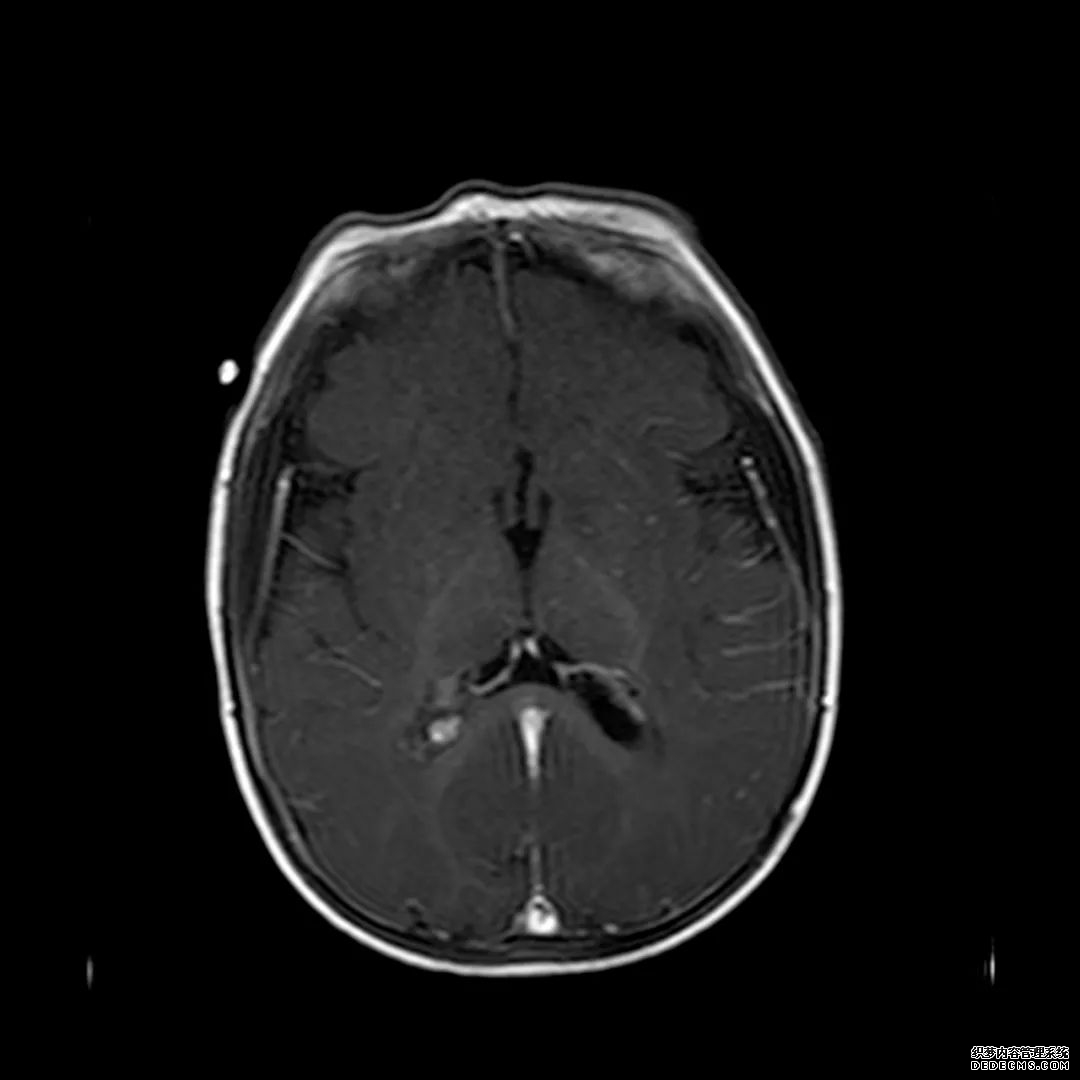

脑MRI显示尾状核、扁豆状核和脑梗头部T2/FLAIR呈双侧对称异常高信号。扩散限制涉及这些区域,其特征是扩散加权DWI(B-1000)上的高强度,ADC图上相应的减弱强度。

印象:通过将这些成像模式与临床和实验室检查结果相结合,就有可能得出低血糖性脑病。